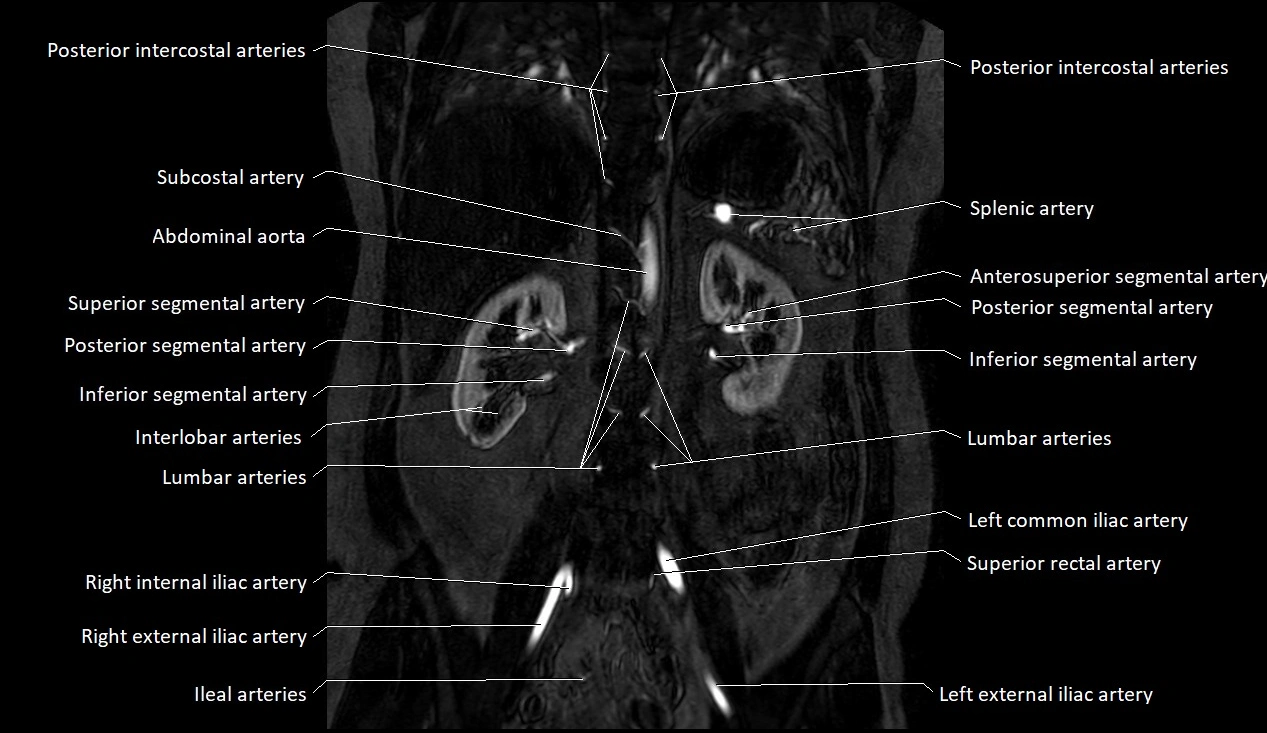

MRA (Magnetic Resonance Angiography):

• Contrast-enhanced MRA provides high-resolution imaging of the aorta and its branches

• Allows 3D reconstruction of visceral, parietal, and terminal branches

• Excellent for evaluating aneurysm size, dissection flap, stenosis, or preoperative planning

• Non-invasive alternative to conventional angiography

MRI images

image